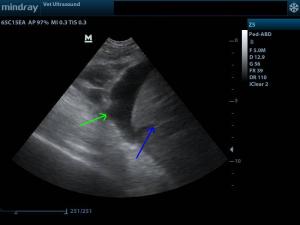

Έγινε υπέρηχος κοιλίας και καρδιάς. Στην κοιλιακή κοιλότητα βρέθηκε παρουσία άφθονου ασκιτικού υγρού.

( πράσινο βέλος ασκιτικό υγρό, μπλέ βέλος λοβοί του ήπατος)

Δεν βρέθηκαν αλλοιώσεις που θα δικαιολογούσαν την παρουσία υγρού στην κοιλιακή κοιλότητα.